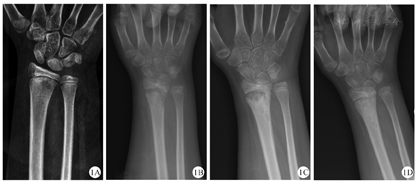

X线是临床上最常用的检查,通常X线在疾病初期无明显改变,随着疾病的进展,X线可显示早期溶骨性病变、硬化、骨扩张或后期呈混合性显像[20,21](图1)。在临床工作中,经验丰富的影像医生才能通过X线检查将CNO与骨肿瘤、感染性骨髓炎鉴别区分。对于无症状的CNO疾病,放射性核素骨显像是常用方法,但因其具有辐射,临床上广泛应用受到限制[22]。MRI是目前最具特异性的影像诊断方法,典型的MRI表现为初期的骨髓水肿,到后期的骨皮质变薄、溶骨性破坏伴硬化(图2、图3、图4)。全身MRI检查在急性炎症期最具有特异性,在MRI可以表现出T1序列低信号和T2序列高信号[21,23]。全身MRI检查在疾病的早期诊断中具有重要的意义,因为它能够在骨溶解、骨硬化之前检测到骨髓水肿和无症状骨病变,并且没有辐射,可用来监测随访骨骼病变的进展演变[24]。(图1、图2、图3、图4中影像学资料均来自同一患者)